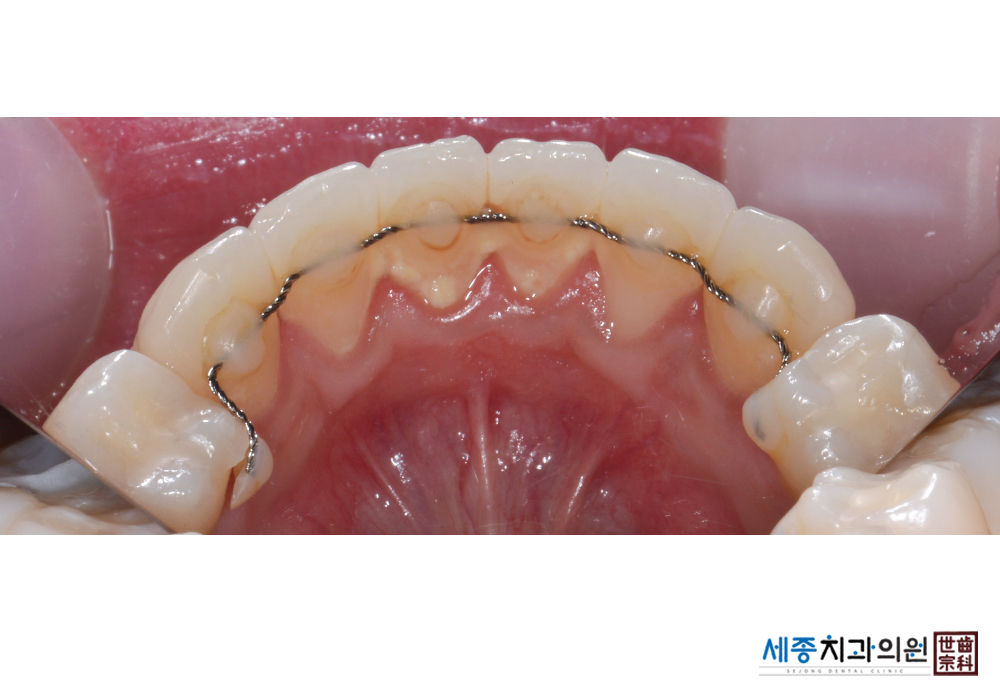

[스케일링] 치주질환 예방 스케일링 치료

치료후 : 2019-03-02

가글마취&저주파 스켈러를 사용한 스케일링